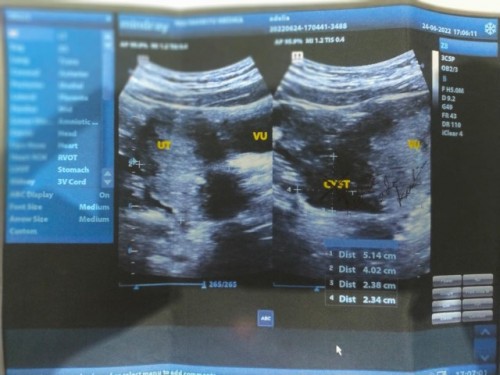

Hasil usg 2 dimensi

Apa ada yg bisa membaca hasil usg apakah saya hamil atau tidak